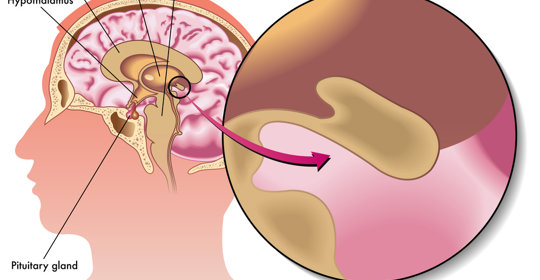

丘腦下部損害:冷敷護理與醫療干預

丘腦下部損害:緊急處理與注意事項

腦下垂體腺瘤:症狀、診斷與治療